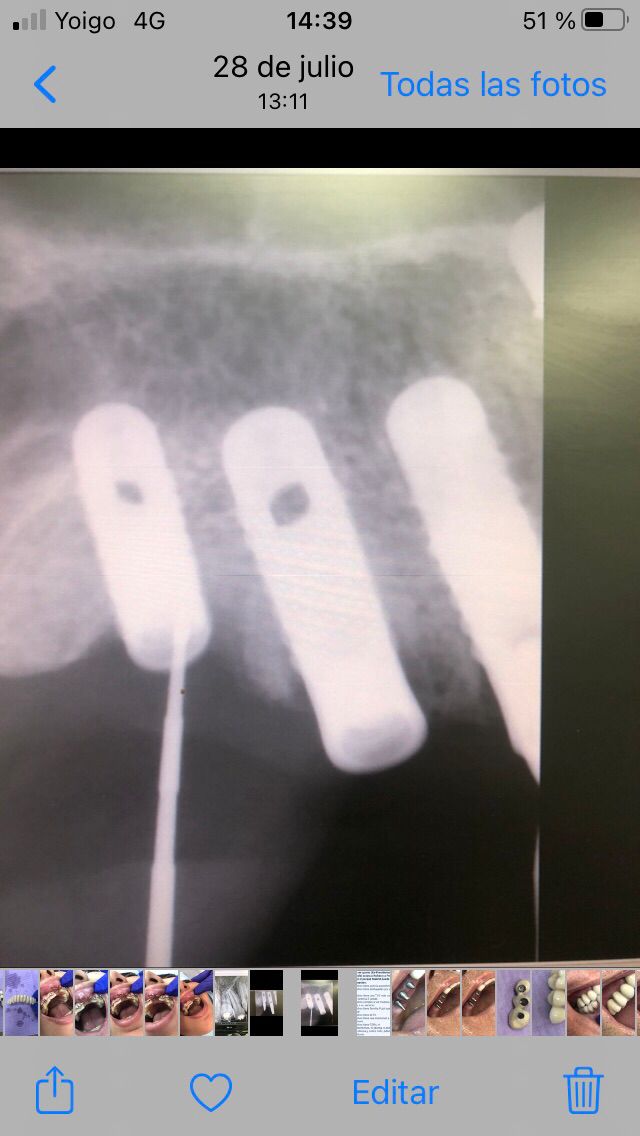

El paciente fue tratado en el año 1994 con una rehabilitación oral. Se instalaron 10 implantes métrica de rosca de conexión 2,3mm : 6 en maxilar superior y 4 en maxilar inferior. En maxilar superior se instalan 3 en segmento distal derecho y 3 en segmento distal izquierdo y permanecen 4 dientes incisivos anteriores superiores como remanente. Con estos 10 apoyos en maxilar superior (3 implantes +4 dientes+3 implantes) se instala una arcada ceramo–metálica superior por segmentos (3+4+3). En mandíbula se instalan 4 implantes en zona distal inferior derecha y una prótesis ceramo–metálica en segmento individual sobre estos 4 implantes, el resto son dientes naturales con coronas ceramo–metálica. Todos los aditamentos utilizados fueron rectos macizos originales de la marca utilizada en aquel momento (titanio grado 3). Así de este modo se realiza la rehabilitación oral.

El paciente no presenta incidencias hasta el año 2005, cuando acude a consulta con el segmento distal derecho desprendido y en el que se había producido una fractura de los aditamentos macizos a nivel de la unión del aditamento con implante, de forma que la rosca fracturada del aditamento está encajada dentro de los implantes.

El tratamiento que se intento fue extraer las roscas rotas con ultrasonidos, pero no se pudo, por lo que procedimos a realizar el vaciado de estas roscas rotas y a realizar unas espiras nuevas en estos vaciados con un set de machos roscantes, para después roscar nuevos aditamentos originales de la casa ya fabricados en aleación de titanio (grado V) . Una vez instalados los aditamentos procedimos a su tallado y a realizar la prótesis ceramo–metálica como tenía antiguamente.

Actualmente vuelve el paciente de nuevo con la misma prótesis. Había roto dos de los tres pilares en concreto los más distales. El primero de los dos había roto la rosca del aditamento dentro del implante como ocurre habitualmente. Pero el ultimo pilar había roto directamente la cabeza del implante tal como se ve en la radiografía y lo que quedaba era un cilindro de titanio macizo perfectamente integrado en el maxilar, sin posibilidad de enroscar nada. Le explicamos al paciente que habría que quitar y poner un implante en el mismo acto. El paciente dijo que no, así que decimos que no se haría cirugía. Buscamos solución alternativa: hacemos un un agujero en el centro del macizo cilíndrico del implante roto y pasamos sucesivamente el set de machos roscantes. Utilizamos una fresa cañón de 1 mm que poco a poco se va introduciendo hasta 8mm con un poco de vagación, que hace que sea un poco mas de 1mm de diámetro. Posteriormente pasamos el conjunto de machos roscantes de métrica 2mm para poder usar un aditamento experimental, que era un palo de rosca de diámetro 2 mm unido a un cuerpo metálico en forma de sombrero napoleónico fabricado en cromo/cobalto, prototipos primitivos de la sistemática ASATIM y que tienen la característica de tener gran resistencia a la fractura. Nos llevó un tiempo largo el tallado de dichos aditamentos, tal como se puede observar en las imágenes, y tras cicatrizar la encía se le hizo una prótesis estándar. Esperemos que no lo rompa más veces.